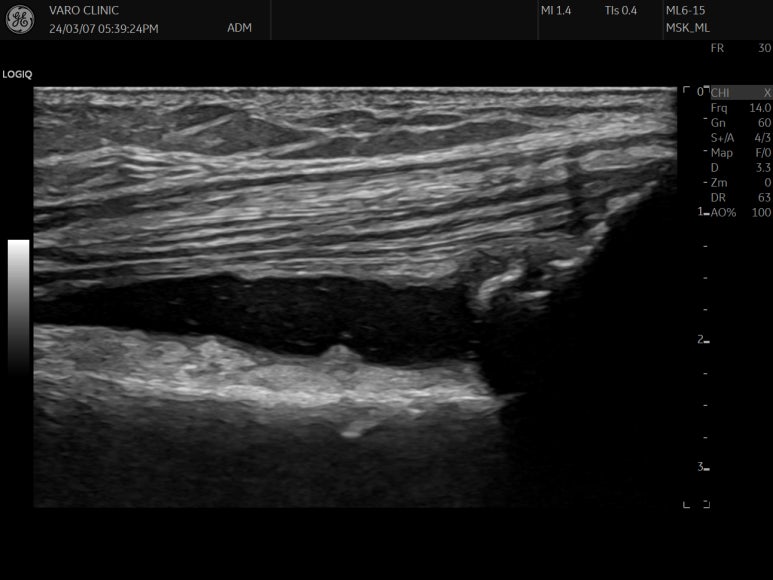

위 영상은

제가 출판한

초음파 전공서적인데요.

대퇴직근의 긴장을 치료하는

핵심 혈자리,

의

표준 초음파 영상입니다.

문제가 있는 혈자리를

손으로 찾은 뒤

최대 효과를 내는 깊이로

초음파 약침을 시술합니다.

근육을 싸고 있는 막을

한 겹 한 겹 떼어내면서

정확한 깊이로 시술합니다.

시술 후 영상을 보면

근막을 따라 약침이 들어간 것을

알 수 있습니다.